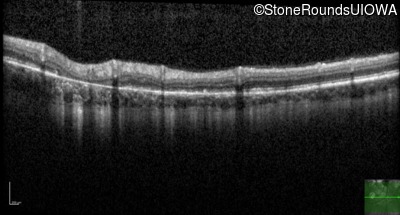

This 31 year old woman had subtle macular abnormalities discovered incidentally earlier that year. Her medical history at the time was unremarkable except for gestational diabetes during her most recent pregnancy. Five years later she was diagnosed with type 2 diabetes managed with oral medication. Two years later she developed sufficient hearing loss that hearing aids were required. Her acuity remained 20/20 OU at that time.

Age at visit: 31 years